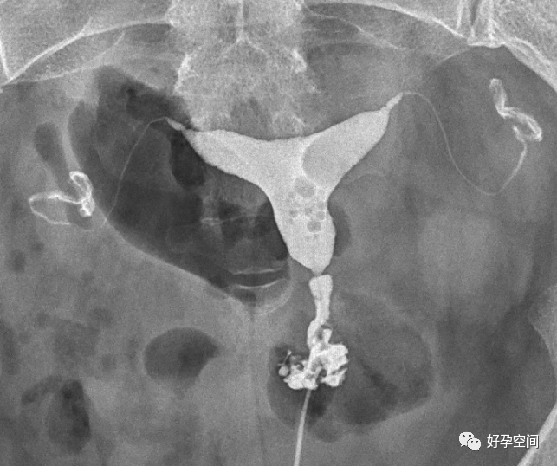

输卵管相

弥散相,延迟5分钟摄片,双侧输卵管内可见较多造影剂

弥散相,延迟10分钟摄片,双侧输卵管内可见少量造影剂

弥散相,延迟20分钟摄片,双侧输卵管内基本没有造影剂残留